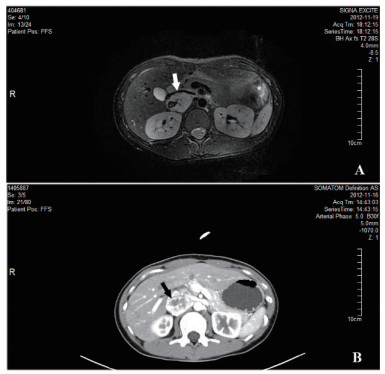

患者2,女,73岁,因“发现血糖升高13年,反复心悸出汗1年”入住我科。入院后监测血糖波动于3.2~22.6 mmol/L,血压波动于77~223/38~90 mmHg。尿VMA 88.20μmol/24h(0.1-68.6)。腹部CT:左侧肾上腺见一不规则肿块,大小35.3 mm×19.9 mm×29.4 mm,考虑嗜铬细胞瘤(图 3)。术前予特拉唑嗪口服4周,血压控制基本平稳。术前24 h血压波动在99~134/55~66 mmHg。手术当日停用特拉唑嗪,全麻下行腹腔镜左肾上腺肿瘤切除术。术中治疗监测血压波动于110~166/42~69,手术过程顺利,持续约50 min,术中出血约10mL。术后转入重症监护室。术后7 h出现血压下降,予扩容及血管活性药物维持血压仍偏低,术后10 h复查血常规血红蛋白45 g/L,较前明显下降,超声提示腹腔内大量积血。考虑腹腔大量出血,行腹膜后探查+血肿清除止血术,术后血红蛋白稳定,血压稳定。手术病理:(左肾上腺)嗜铬细胞瘤。出院时血压126/70 mmHg左右,未使用降压药物。予甘精胰岛素、阿卡波糖及西格列汀控制血糖,血糖控制在8~10 mmol/L左右。

| 图 2 腹部CT:左侧肾上腺见一不规则肿块,大小35.3 mm×19.9 mm×29.4 mm(前后×左右×上下),边界清,平扫密度不均,增强扫描明显不均匀强化,中心见不规则囊变坏死区,提示左侧肾上腺占位,考虑嗜铬细胞瘤(箭头) |